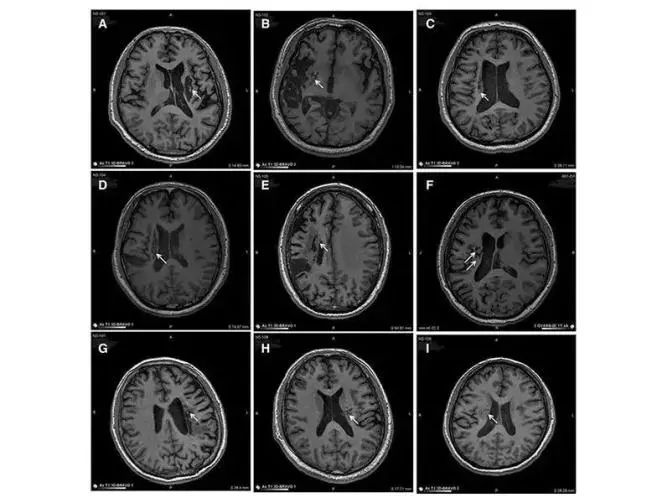

中風(fēng)可導(dǎo)致神經(jīng)元損傷。對(duì)干細(xì)胞轉(zhuǎn)運(yùn) MED 的研究表明,干細(xì)胞可以再生和修復(fù)受損的腦神經(jīng)元,從而減少中風(fēng)患者的后遺癥癥狀。在 9 名不同年齡的腦卒中偏癱患者中,將干細(xì)胞移植到腦梗塞區(qū)域取得了顯著的臨床效果。

9 名患者的成像顯示病變區(qū)域的組織發(fā)生了顯著變化。影像學(xué)顯示,移植到腦梗死病變中的干細(xì)胞分化為神經(jīng)系統(tǒng)的各種細(xì)胞,分泌營(yíng)養(yǎng)因子,促進(jìn)神經(jīng)和血管再生,修復(fù)受損的血腦液屏障,減少炎癥反應(yīng),促進(jìn)腦梗死動(dòng)物神經(jīng)功能的恢復(fù)。結(jié)果,9 名臨床患者的偏癱癥狀明顯改善。